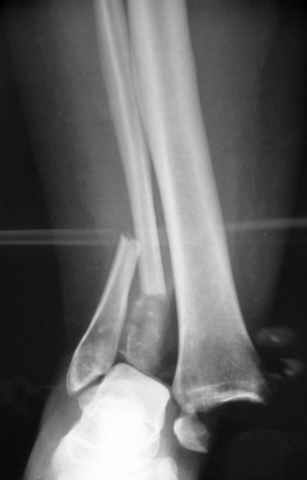

Pilon fracture:

-Появляется ориентир и остов, на чем можно строить восстановление, почему сперва малоберцовую, впервые обьяснили и описали (Pylon type and Ankle fractures) в середине 50х Rienau и Gay.

Восстановливая длину и ротацию малоберцовой кости, затем относительно легче произвести реставрацию остальных элементов перелома дистального эпиметафиза болшеберцовой кости.

где исследования на трупах показали, что малоберцовая кость участвует в стабильности голеностопного сустава, поддерживая наклон тарана (talar tilt) за счет связок. После ознакомления работой Ramsey в ортопедию ввели термин "при переломах голеностопного сустава смещенная

таранная кость следует за малоберцовой костью" т.е. связка не рвется, а тянет таран за собой, поэтому восстановление малоберцовой кости в

первую очередь, затем остальных элементов - стал классическим при лечении данной патолгии. Латеральная колонна (столб), дистальный

конец малоберцевой кости, к нему прикрепляется латеральный суставной фрагмент дистального эпиметафиза большеберцовой кости (как на снимке)

и таранная кость, которые при репозиции малоберцовой кости репонируются автоматически.